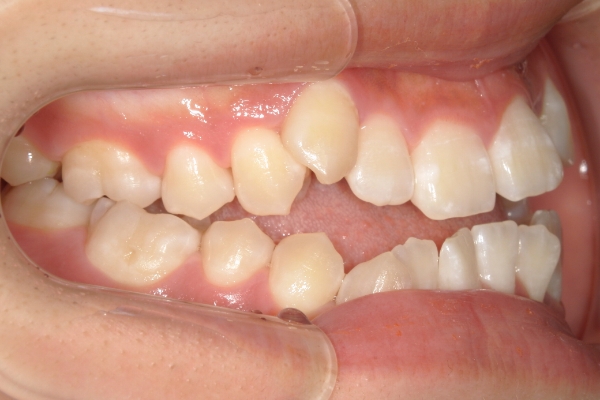

BEFORE

治療前

PROCESS

3か月

AFTER

治療後

骨格的に下あごが前下方に長いことが原因で、受け口、開咬(前歯が当たらない)の症状がでていました。また下あごが右にずれており、その影響で上下の歯列正中(真ん中)の大きなずれも生じていました。顎変形症手術も選択肢の一つでしたが、患者さまの希望もあり、下顎左側小臼歯の抜歯をして通常の歯列矯正で治療をしました。

治療後は、前歯、奥歯の噛み合わせが整い、上下の歯列の真ん中が一致しました。歯列全体のアーチも安定し、機能面・審美面のどちらも大きく改善されました。